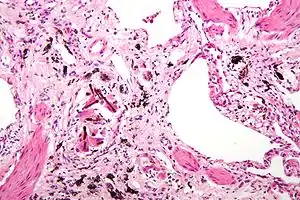

Pneumoconiose é uma doença pulmonar ocupacional com padrão restritivo causada pela inalação de poeiras inorgânicas, geralmente associada a trabalho em metalúrgicas, construtoras, mecânicas ou minas.

Radiografia do tórax pode mostrar uma característica desigual, subpleurais, bibasilar infiltrados intersticiais ou pequenas radiolucencies cística chamada faveolamento.